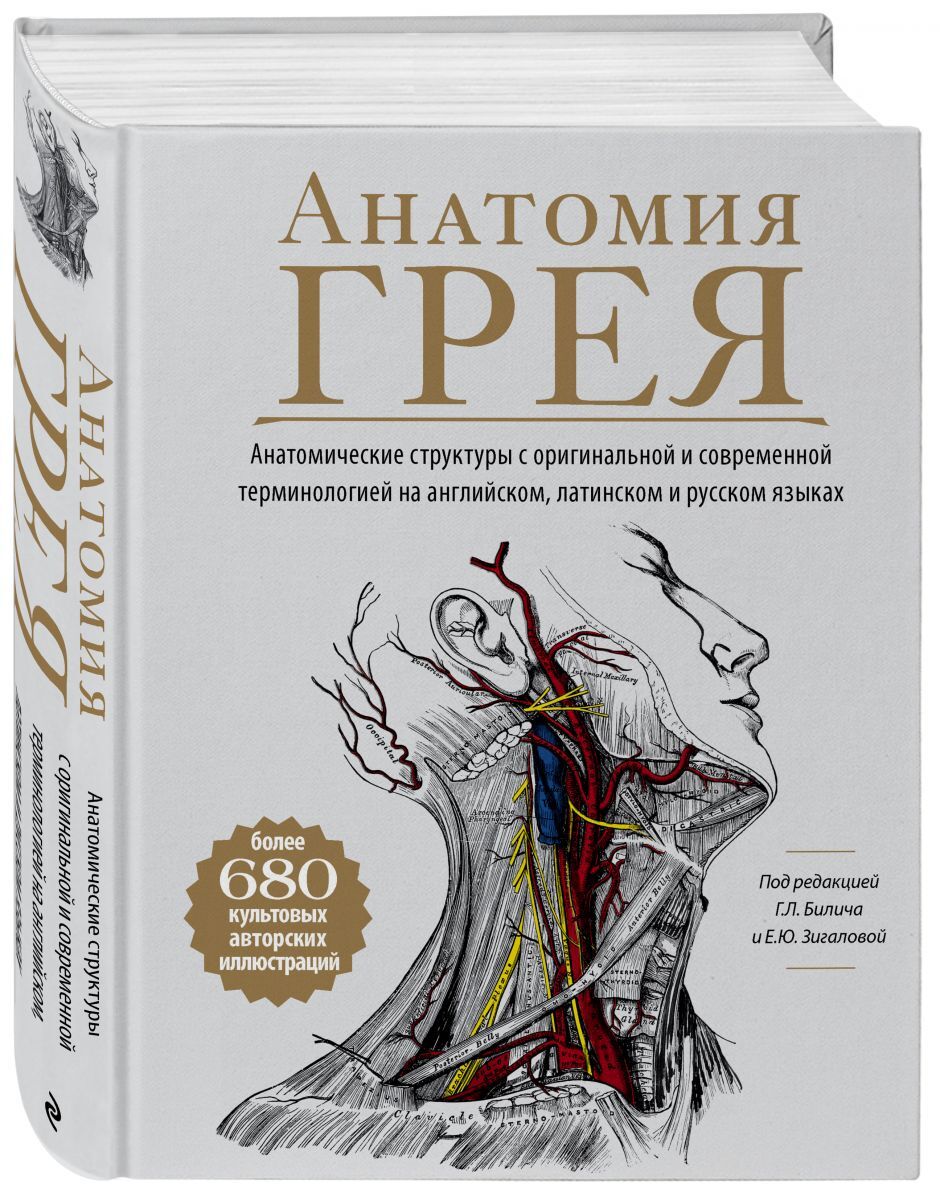

Написанная в 1850-х годах молодым врачом Генри Греем, "Анатомия Грея" была самой всеобъемлющей и доступной анатомией своего времени. Книга, которую вы держите в руках, содержит исторический текст второго издания и все авторские рисунки Генри Вандайка Карт

Написанная в 1850-х годах молодым врачом Генри Греем, "Анатомия Грея" была самой всеобъемлющей и доступной анатомией своего времени. Книга, которую вы держите в руках, содержит исторический текст второго издания и все авторские рисунки Генри Вандайка Карт

АвторБилич Габриэль Лазаревич, Зигалова Елена Юрьевна

ИздательствоЭКСМО

СерияМедицинский атлас: культовый бестселлер

Год выпуска2021

Тип обложкиТвердый переплет

ISBN978-5-699-94048-6

Количество страниц832

Размеры, мм252х196х46

Вес с упаковкой, г1620